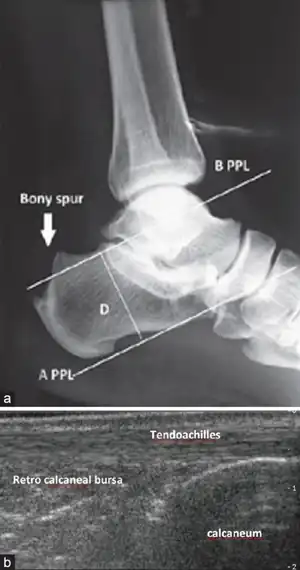

| Preoperative X-ray ankle joint lateral view showing (a) the parallel pitch lines (PPLs) determine the prominence of the bony projection. (b) Ultrasound ankle showing Achilles Tendon, Retrocalcaneal bursa and Calcaneum | |